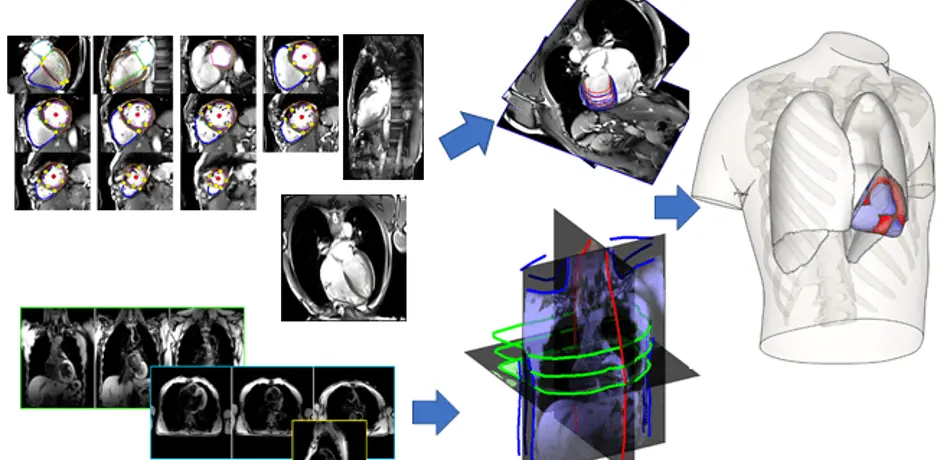

Grau Group

Our research focuses on the development of biomedical image analysis algorithms, with an emphasis on the combination with computational models, and applications on cardiac and pulmonary medicine.